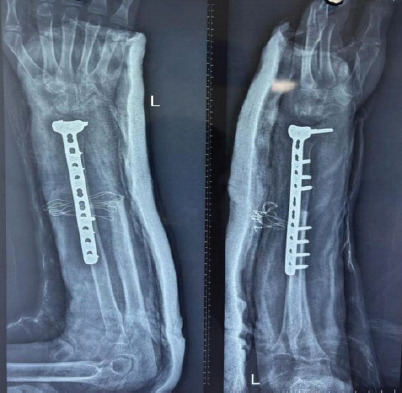

Case report: This case report describes a young skeletally immature female presenting with a Campanacci grade 3 GCT of the distal radius, characterized an osteolytic lesion sparing the epiphysis. Following biopsy confirmation, the patient underwent wide local excision of the tumor with ulnar translocation, fixed using a distal radius locking plate to preserve joint integrity. Post-operative rehabilitation included physiotherapy to restore wrist mobility and grip strength.

Results: At 2 years post-surgery, the patient demonstrated no re-occurrence of tumor and satisfactory functional outcomes, including 90° dorsiflexion, 35° palmar flexion, 60° pronosupination, and 68% grip strength compared to the contralateral side.